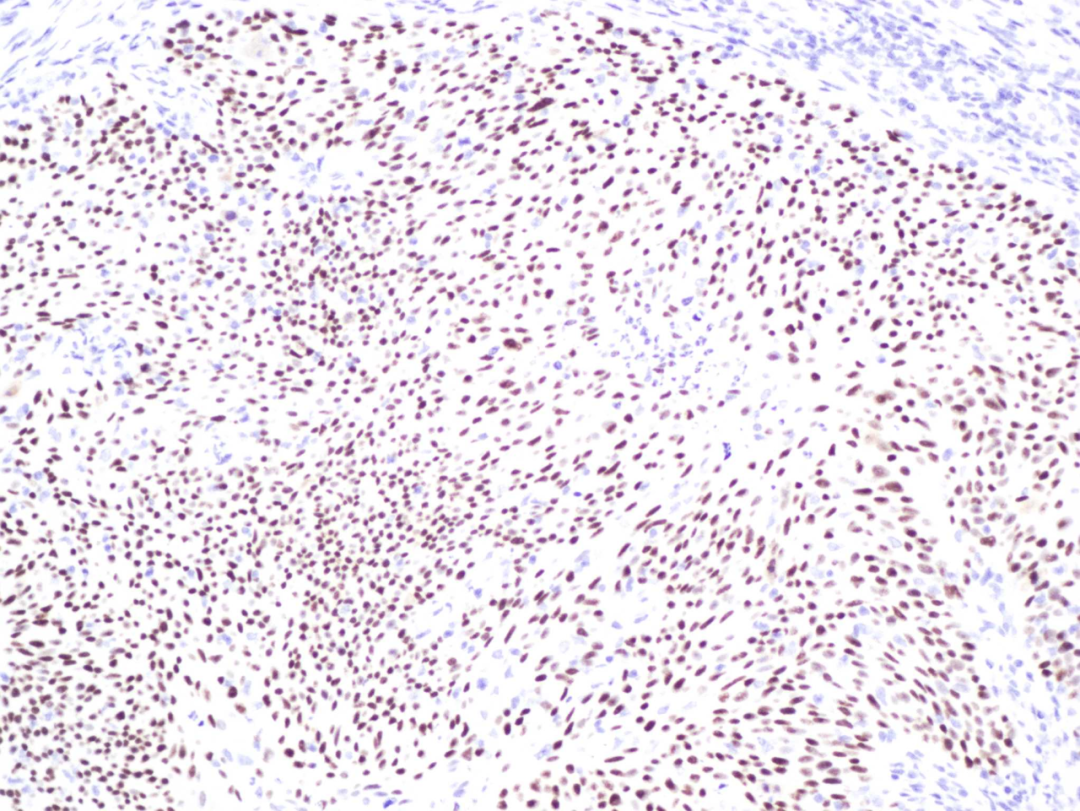

(肿瘤细胞核阳性表达)

免疫组化,全称免疫组织化学技术(immunohistochemistry,IHC),利用抗原与抗体特异性结合原理,通过化学反应使标记抗体的显色剂显色来确定组织细胞内抗原,对其定位、定性及定量的研究。

简单说来,人体细胞中存在多种的蛋白质,这些蛋白质承担着细胞的许多功能,包括细胞的增殖和分化、能量转换、信号转导及物质运输等。在检测过程中,利用“抗原抗体结合”原理,促使显色抗体与细胞蛋白(目标抗原)结合,再通过显微镜观察,就能准确知道目标细胞是否表达了相关蛋白、具体表达了多少这种蛋白质。可以更清楚地了解肿瘤细胞的侵袭能力,更可以针对含量丰富的蛋白使用特定的药物,从而精准杀伤肿瘤细胞,使患者获益最大化。